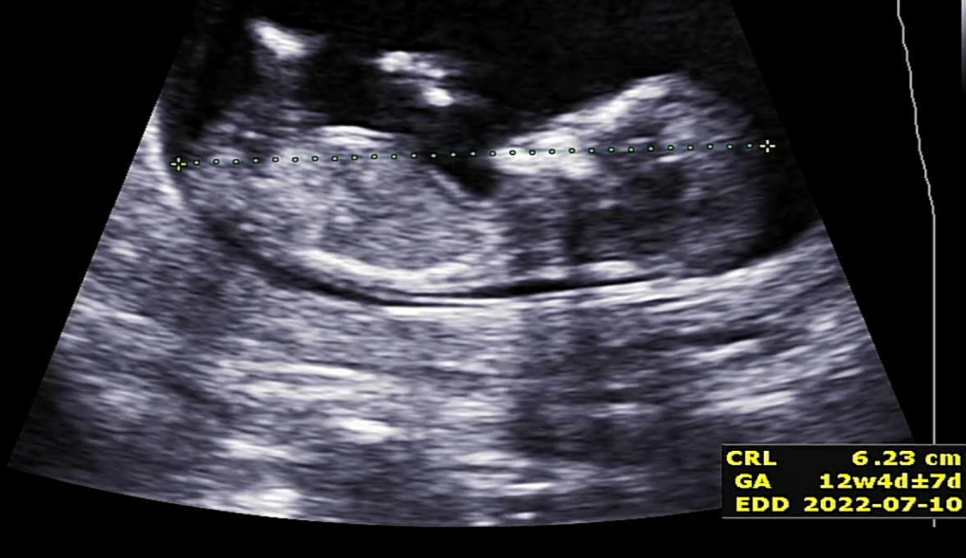

우선 1차기형아검사 초음파에서 제일 먼저 확인했던 머리~꼬리뼈의 길이 ㅎㅎ #임신 12주차 정도가 되면 6~7cm 정도가 된다고 합니다. ^^

이렇게 오늘은 1차 기형아 검사 후기를 써봤습니다#1. 차기형 검사 결과는 다행히 문제가 없었습니다 초음파로는 뇌 발달, 콧날이 발달했는지, 목구멍 투명대 검사, 아기의 크기, 심장 박동 정도를 보는 것 같습니다. 입체 초음파 사진도 찍어주세요~